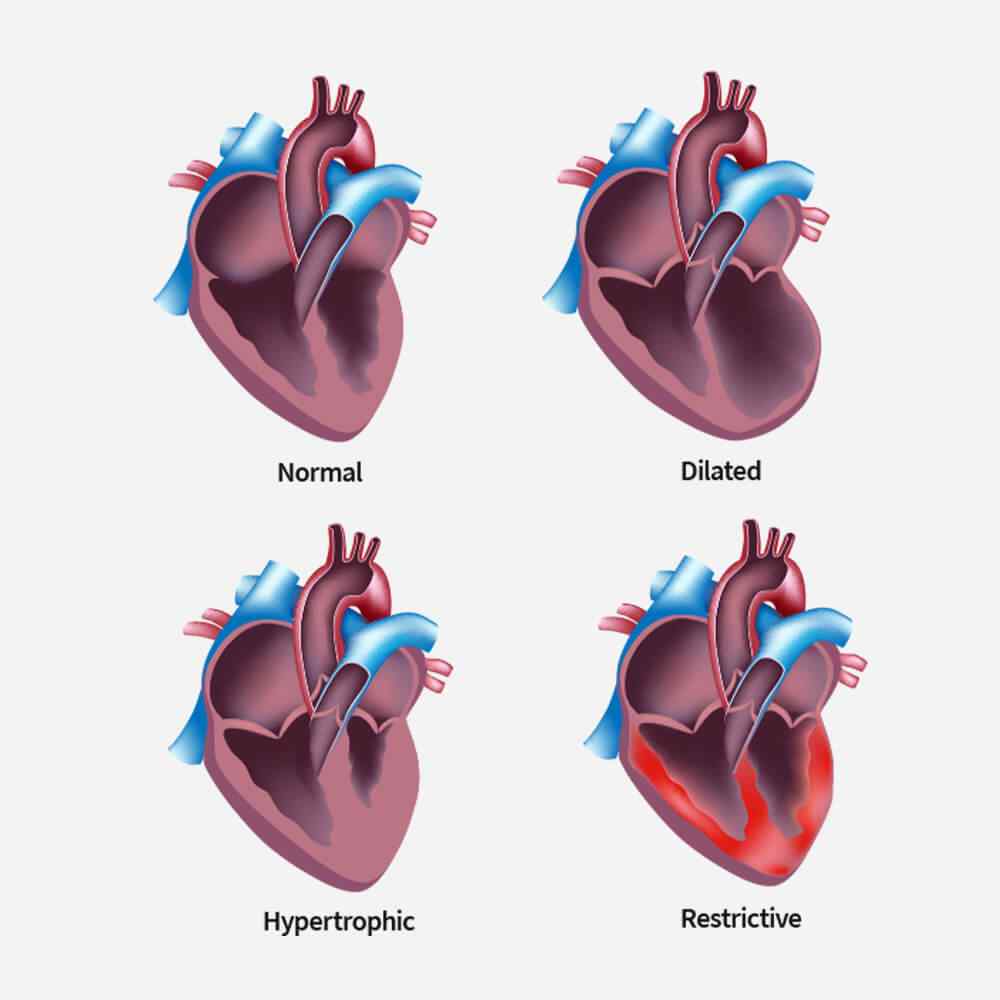

Types of Cardiomyopathy

Restrictive cardiomyopathy is a condition where your ventricles do not thicken, yet they still become stiff and rigid and cannot pump blood effectively.

In this type of cardiomyopathy, the pumping ability of your heart’s main pumping chamber — the left ventricle — becomes enlarged (dilated) and can’t effectively pump blood out of the heart.

This type involves abnormal thickening of your heart muscle, which makes it harder for the heart to work. It mostly affects the muscle of your heart’s main pumping chamber (left ventricle).

In this rare type of cardiomyopathy, the muscle in the lower right heart chamber (right ventricle) is replaced by scar tissue, which can lead to heart rhythm problems. It’s often caused by genetic mutations.